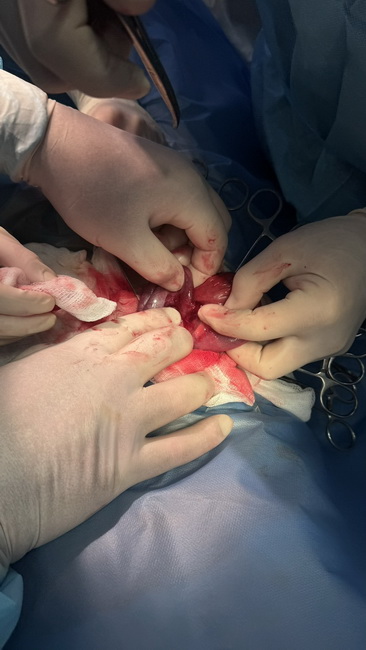

«Під час оперативного втручання з кишківника було успішно видалено магніти, що злиплися між собою, прикрасу, а також серветкові залишки, які дитина ймовірно проковтнула раніше. Окрім сторонніх тіл було виявлено множинні перфорації стінки кишки. На жаль, деяку частину кишки довелось видалити, але післяопераційний період пройшов без ускладнень. Нині стан дитини задовільний. Хлопчик виписаний додому під спостереження батьків та сімейного лікаря», – йдеться в повідомленні.